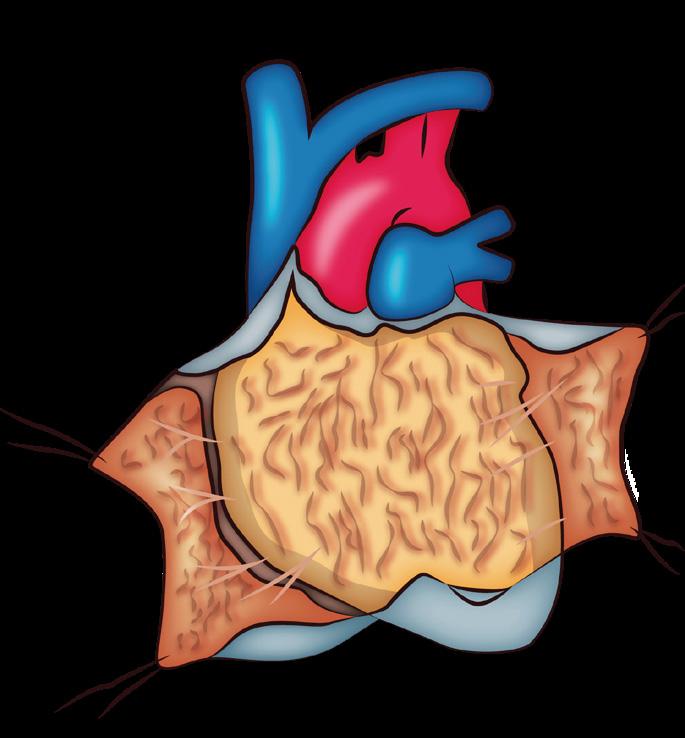

Definición

Son patologías intrínsecas del miocardio, generalmente primarias (etiología desconocida).